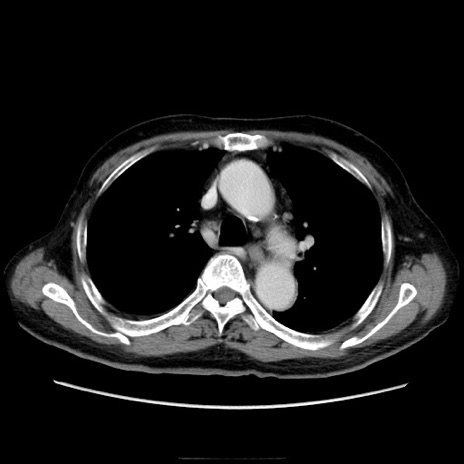

冠状断像

【症例】70歳代男性

【主訴】腹痛

【現病歴】肝硬変・肝細胞癌にてかかりつけの方。約9時間前に食後より腹痛出現。症状が徐々に増悪し、嘔吐出現したため来院。

【既往歴】肝硬変、肝細胞癌(RFA、TACE後)

【身体所見】意識清明、表情苦悶様、BT 36℃、BP 129/78mmHg、P 88bpm、SpO2 97%(RA)、右上腹部から心窩部にかけて圧痛あり、反跳痛なし、筋性防御あり。

【データ】WBC 5800、CRP 0.16